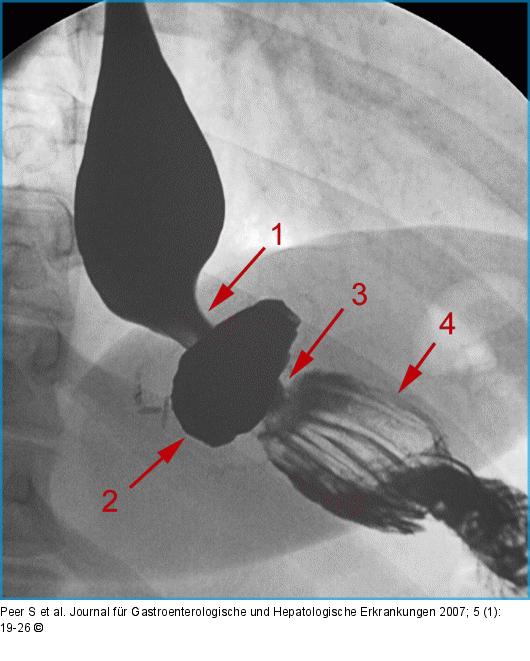

Abbildung 13: Roux-Y-Magenbypass Normalbefund nach Roux-Y-Magenbypass (LPO-Projektion): Gastroösophagealer Übergang (1), Restmagen (2), Magen- Outlet (3), Roux-Schlinge (4). Beachte die in dieser Projektion optimal einsehbare Anastomose zwischen Restmagen und Roux- Schlinge (3). |

Abbildung 13: Roux-Y-Magenbypass

Normalbefund nach Roux-Y-Magenbypass (LPO-Projektion): Gastroösophagealer Übergang (1), Restmagen (2), Magen- Outlet (3), Roux-Schlinge (4). Beachte die in dieser Projektion optimal einsehbare Anastomose zwischen Restmagen und Roux- Schlinge (3). |